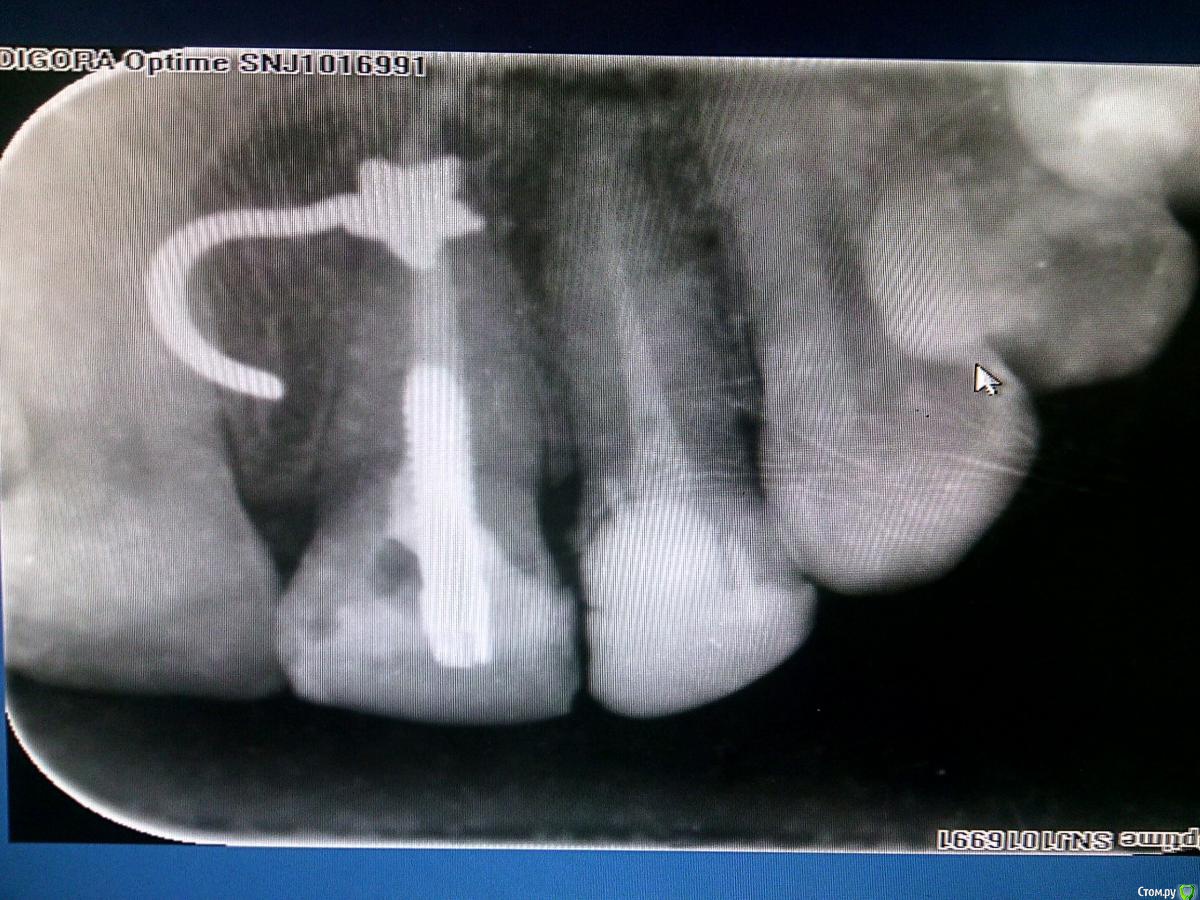

___49___ Опубликовано 25 ноября, 2016 Автор Поделиться Опубликовано 25 ноября, 2016 Угадайте, что это ? Ссылка на комментарий

Большой Зеленый Опубликовано 25 ноября, 2016 Поделиться Опубликовано 25 ноября, 2016 Угадайте, что это ? Пирсинг 3 Ссылка на комментарий

Lodkin666 Опубликовано 25 ноября, 2016 Поделиться Опубликовано 25 ноября, 2016 Пирсинг Ссылка на комментарий

___49___ Опубликовано 25 ноября, 2016 Автор Поделиться Опубликовано 25 ноября, 2016 Абсолютно верно - пирсинг . Ссылка на комментарий

IvanK Опубликовано 25 ноября, 2016 Поделиться Опубликовано 25 ноября, 2016 Пирсингзвездочка или цветочек))) 1 Ссылка на комментарий